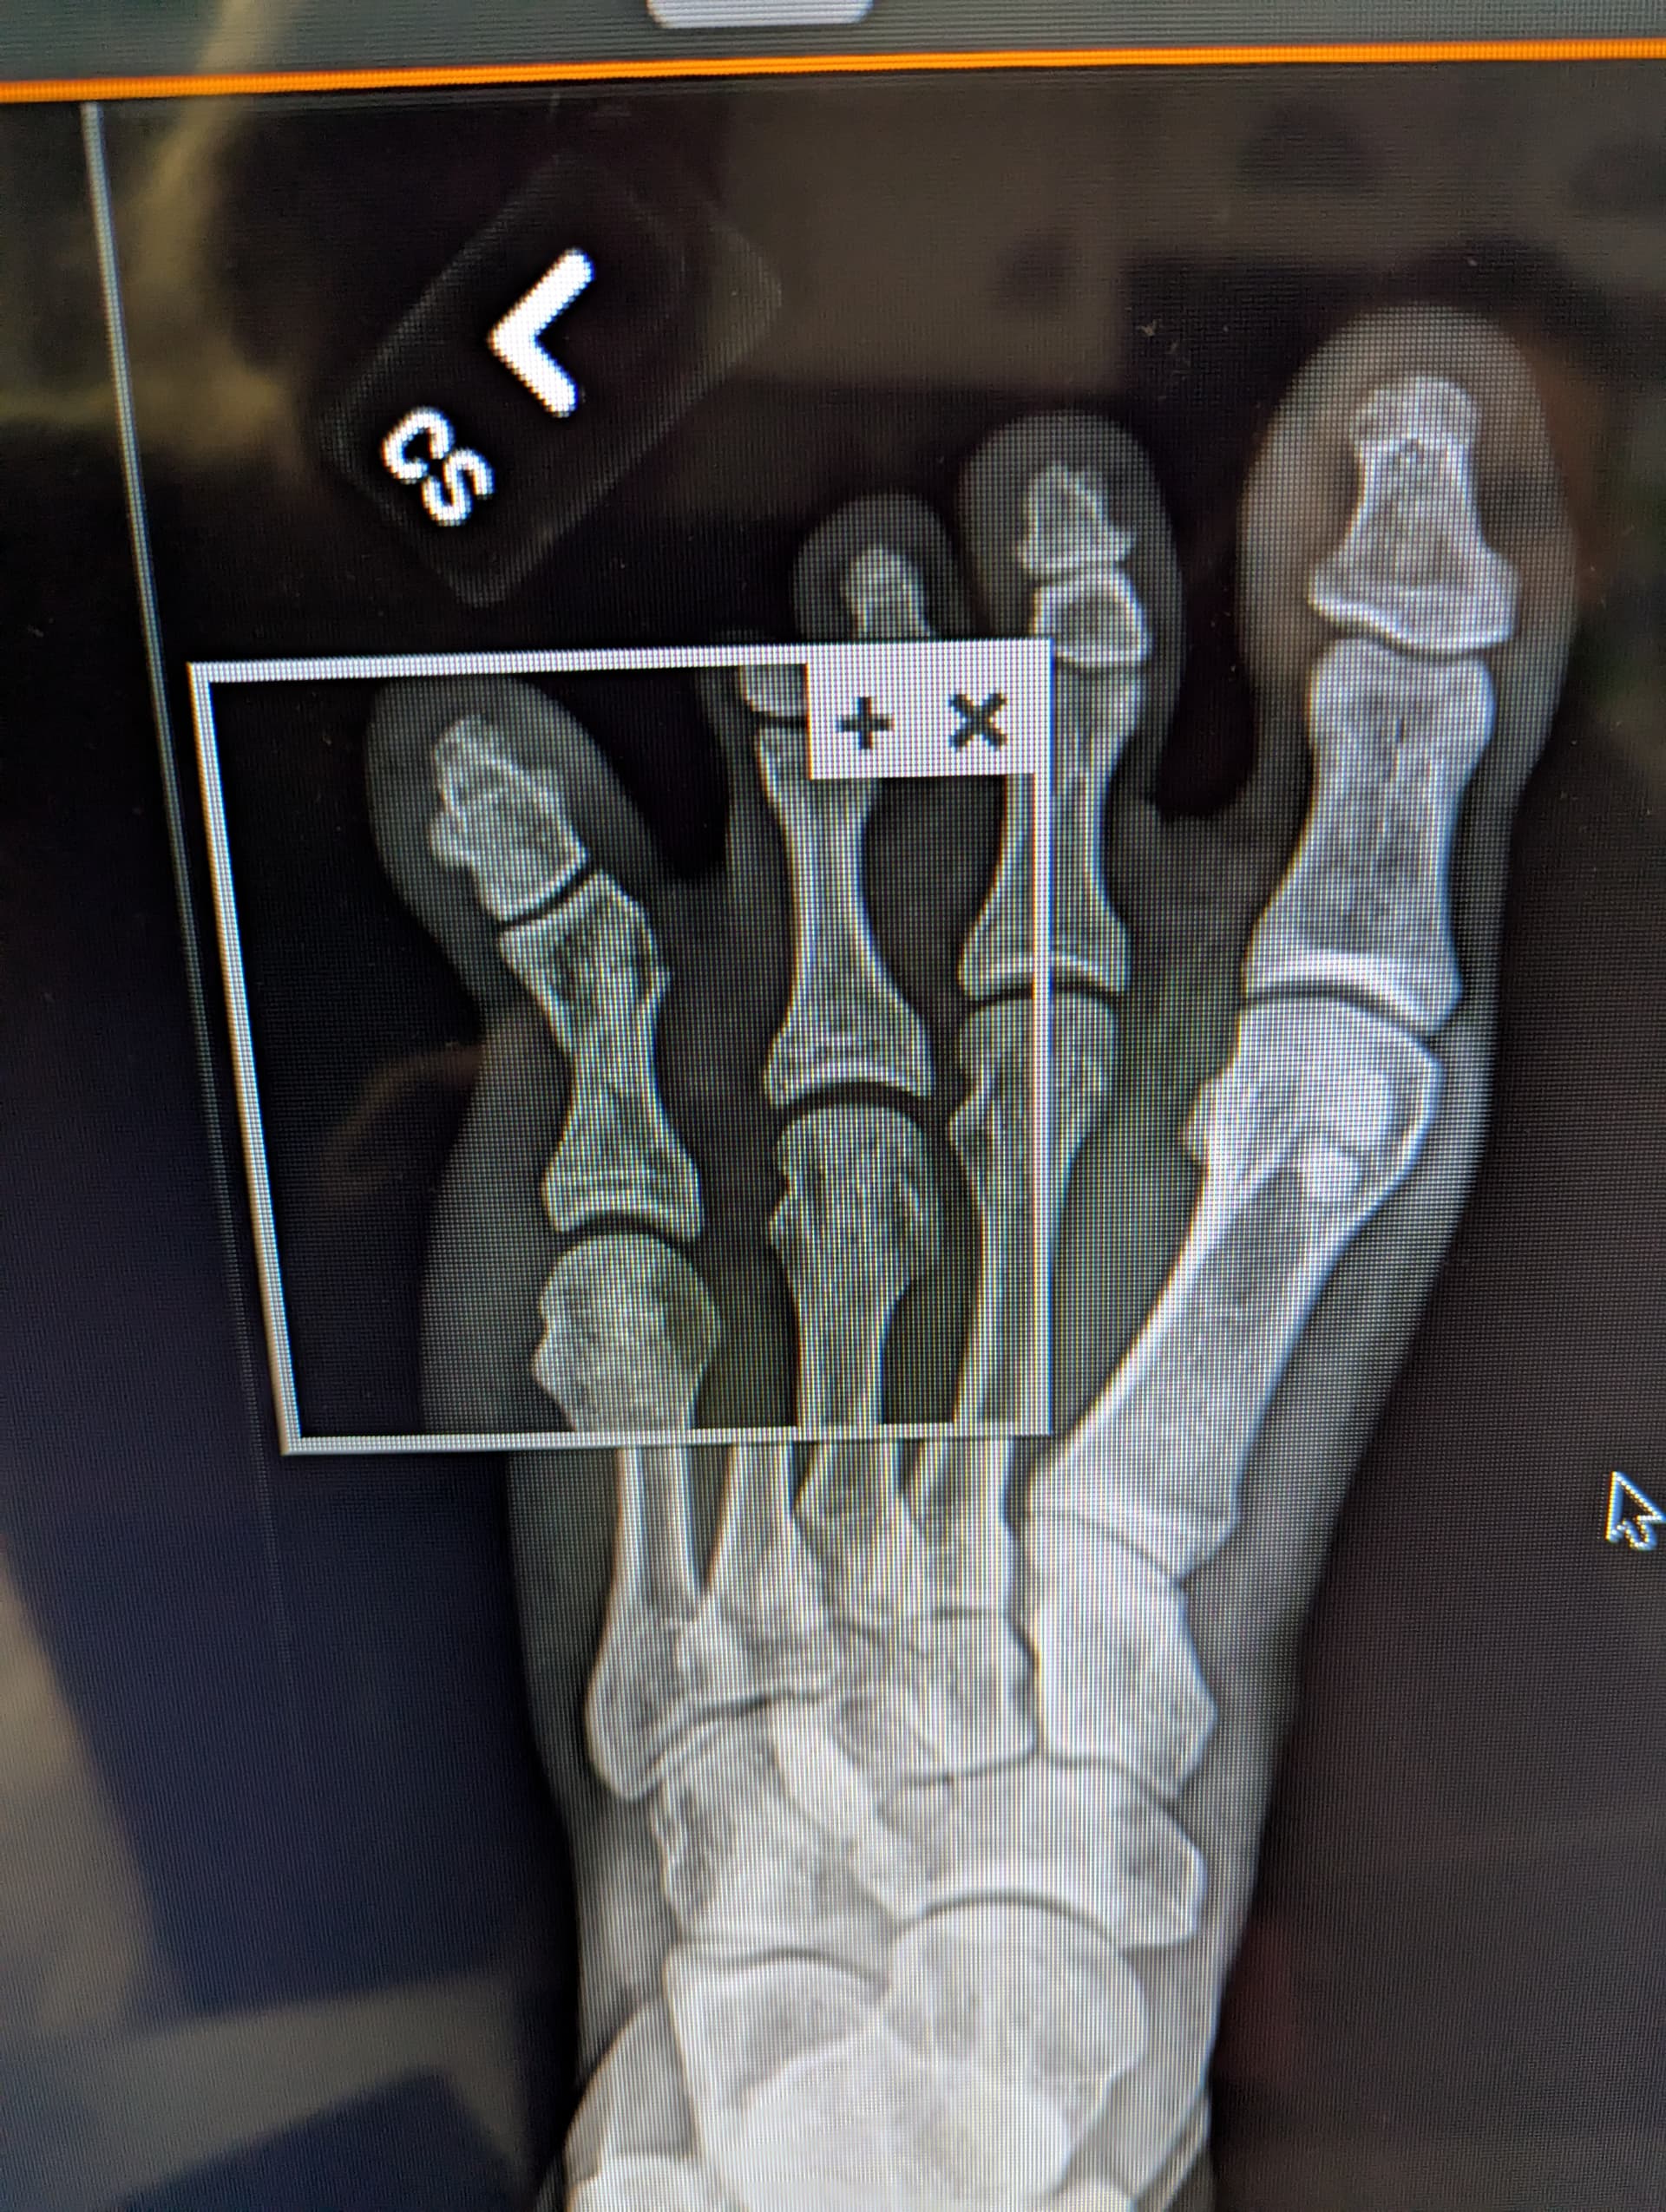

Hello Doctors, I have been slowly losing weight, improving my cardio conditioning, and kind of stalled at my lifting. But I just stubbed my toe and I am trying to figure if I can manage any cardio at all at the moment. I have access to a rowing machine and a skierg at my gym, maybe some type of one legged row, but even standing for the erg is going to be rough right now.

I meeting an orthopedic surgeon Monday. Will need a pin.

No surgery needed. No heavy squats or deadlifts for two weeks, no jumping, no treadmill. Cleared to use a rower.